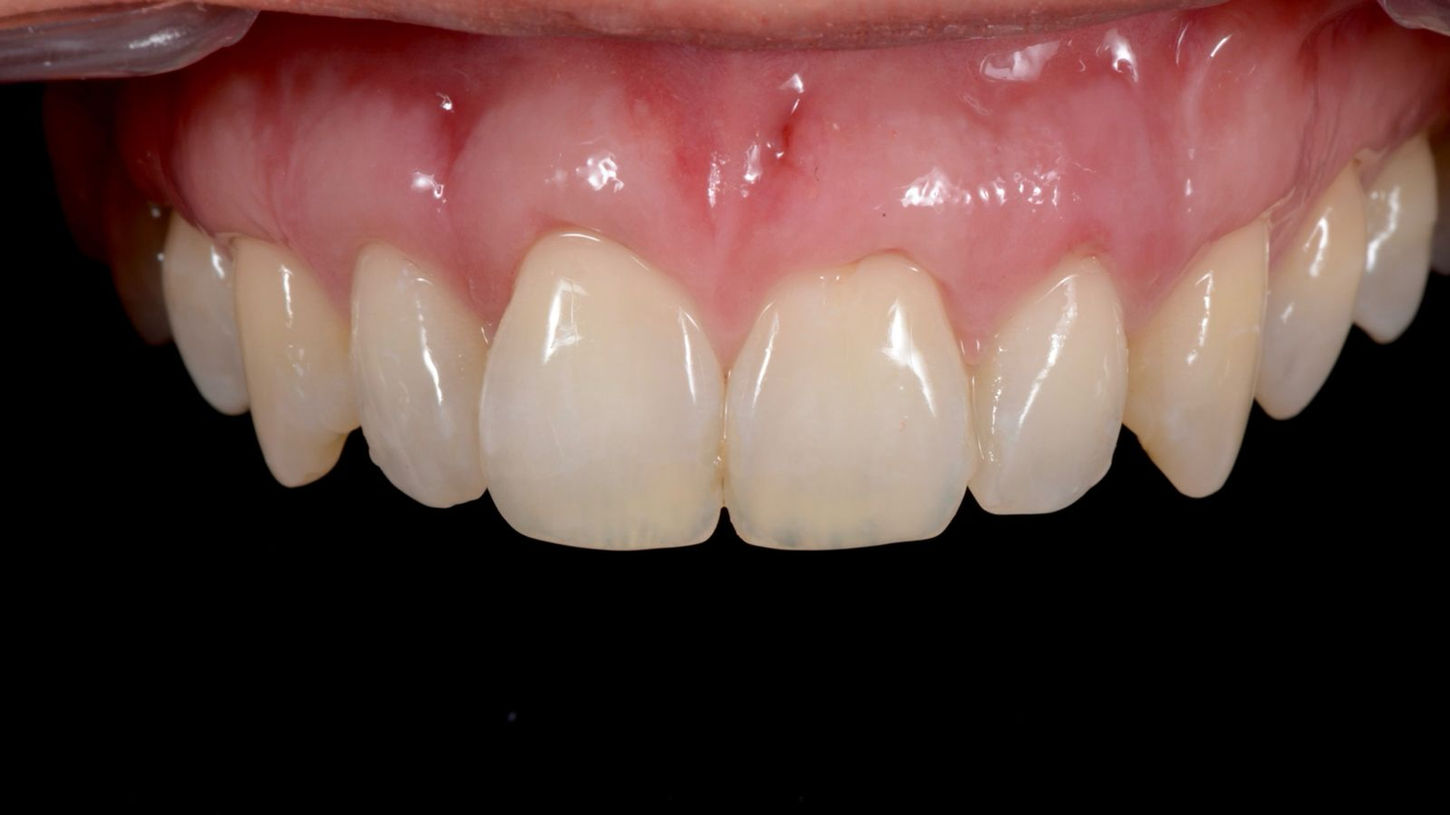

Avant / Après – Traitement des récessions gingivales et recouvrement radiculaire au maxillaire à Embrun

Résultat : Une esthétique dentaire et un confort retrouvés

Patiente de 42 ans, habitante de Gap, est venue consulter le Cabinet Dentaire ASV à Embrun pour des récessions gingivales importantes au maxillaire. En plus d'affecter l'esthétique du sourire l'exposition des racines entraine une hypersensibilité dentaire.

- Recouvrement radiculaire pour protéger les racines exposées

- Renforcement du parodonte par greffe gingivale pour stabiliser les gencives